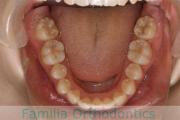

No.22V-409

- 叢生

- 16歳

- 女性

- 上:

- 44

- 下:

- 8|58

- 主な使用装置:

- FEA

- 治療にかかった費用:

- 86万円

八重歯を治したいということで来院されました。下あごの左ずれのある上顎前突(出っ歯)・叢生(でこぼこ)でしたので、上は左右から、下はで左のみ小臼歯を抜歯して、歯科矯正用アンカースクリューとマルチブラケット法にて治療を行いました。2年強、30回程度の通院が必要でした。

上下とも前歯の叢生(でこぼこ、凹凸、ガタガタ)があるため、保定を怠ると後戻りのリスクがあります。